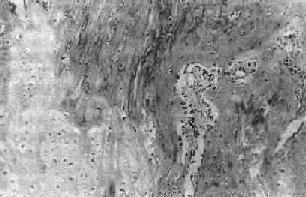

骨折愈合过程的进一步发展,是骨母细胞产生新生骨质逐渐取代上述纤维性骨痂。开始形成的骨质为类骨组织(图17-1),以后发生钙盐沉着,形成编织骨(woven bone),即骨性骨痂(图17-2)。纤维性骨痂内的软骨组织,和骨发育时的软骨化骨一样,发生钙盐沉着而演变为骨组织,参与骨性骨痂的形成。此时所形成的编织骨,由于其结构不够致密,骨小梁排列比较紊乱,故仍达不到正常功能需要。

图17-1 骨痂

左侧为软骨性骨痂,右侧为类骨组织